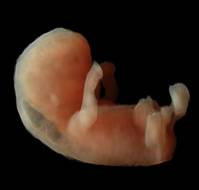

AbstractExomphalos (omphalocele) is a congenital anterior abdominal wall defect characterized by herniation of abdominal viscera into the base of the umbilical cord,..

Omphalocele (exomphalos) is a congenital anterior abdominal wall defect frequently associated with chromosomal or structural anomalies. Environmental and infectious ..